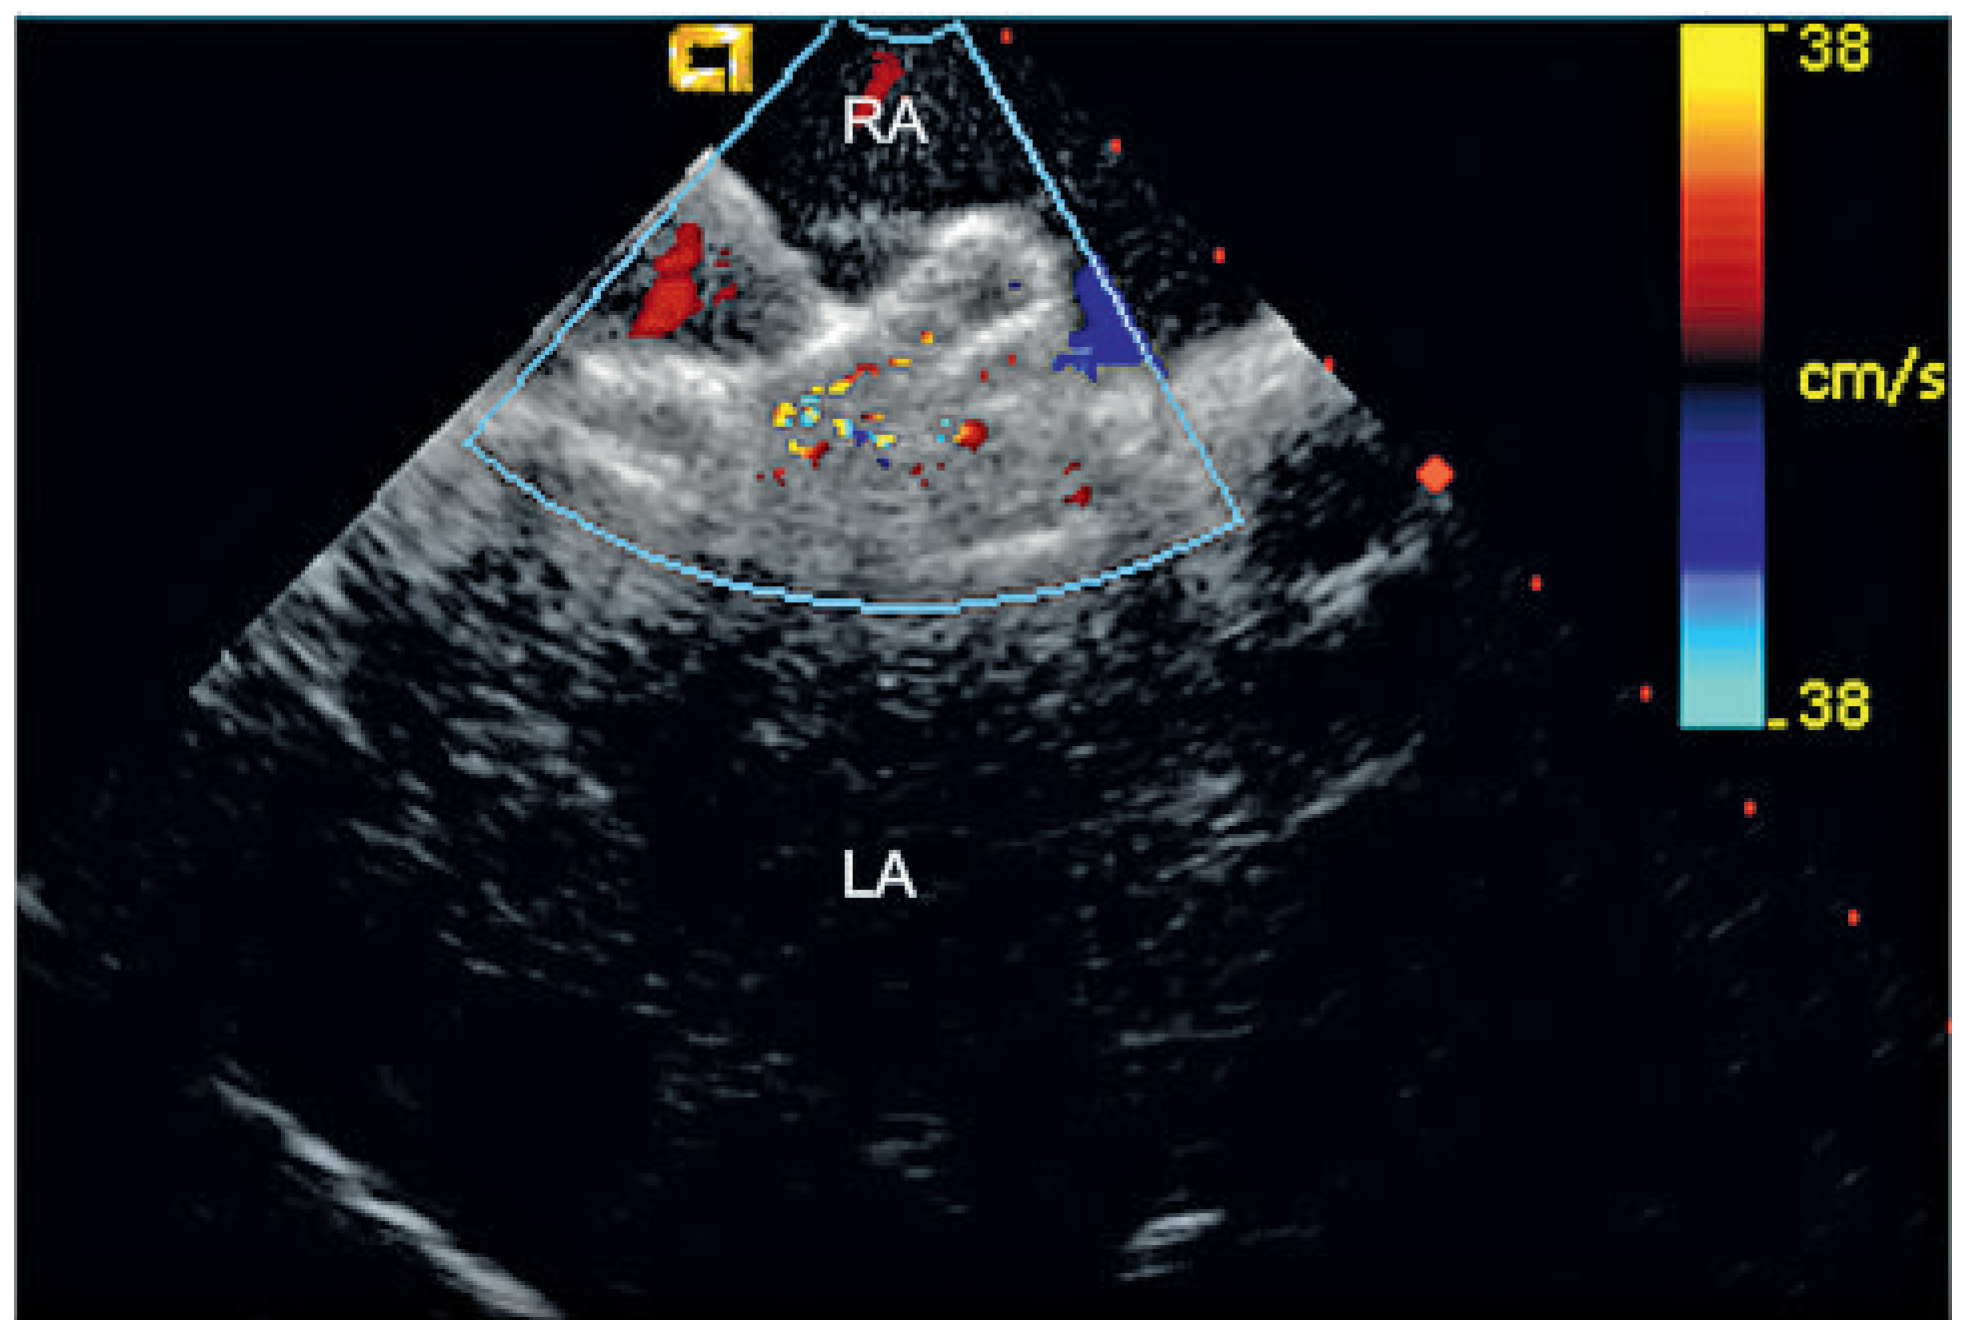

Percutaneous Implantation of an ASD Occluder with Intracardiac Ultrasound